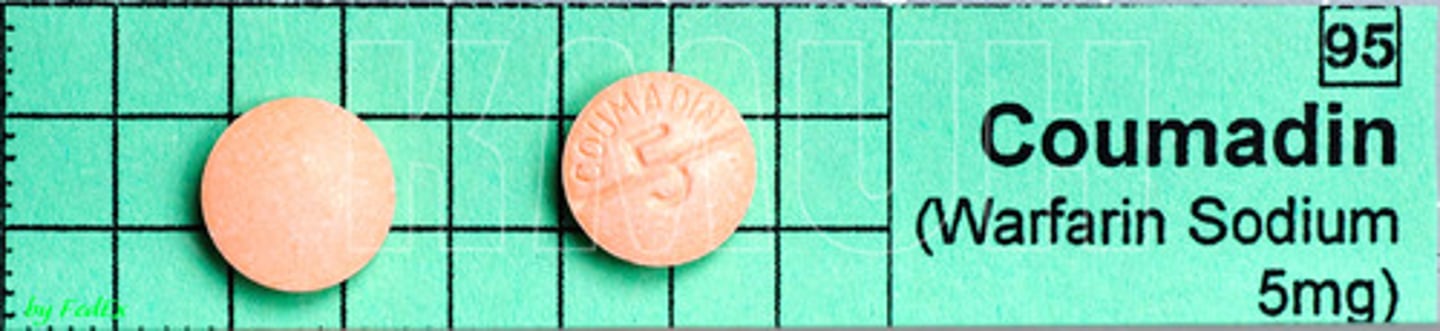

Warfarin

Brand: Coumadin

Class: Vitamin K Antagonist

Drug Interactions: NSAIDs, Antibiotics, Fish Oil, Coenzyme 10, Garlic Supplements, Ginko Biloba, Vitamin K

Side Effects: Excessive bruising / bleeding

Contraindication: Pregnancy Category X

Indication: Anticoagulation, Blood Thinner

Schedule: NCLM